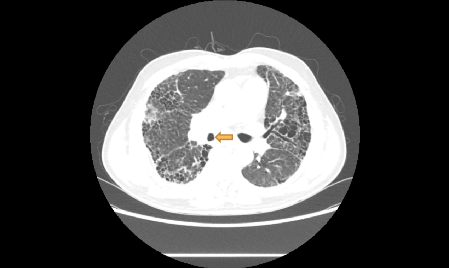

一名70岁的男性患者因“反复咳嗽、咳痰3年,加重2月余”到我院就诊,胸部增强CT提示双肺间质性肺炎、右肺下叶肺癌并纵隔淋巴结转移。

右主支气管狭窄,肺间质纤维化(黄色箭头为隆突下淋巴结肿大)

黄色箭头为隆突下淋巴结肿大